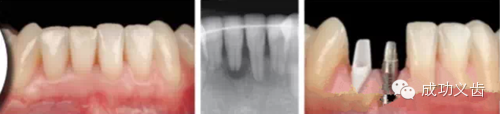

图5.Nobel Replace种植前。联合正畸治疗,以常用的Nobel Replace系统,来修复这个病例。

图6.Nobel Replace种植后。可见缺失的双侧切牙好像从牙龈里生长出来的一样。漂亮的外科、精心的软组织维护、极致的修复、和完善的口内摄影,成就了这个完美的病例。